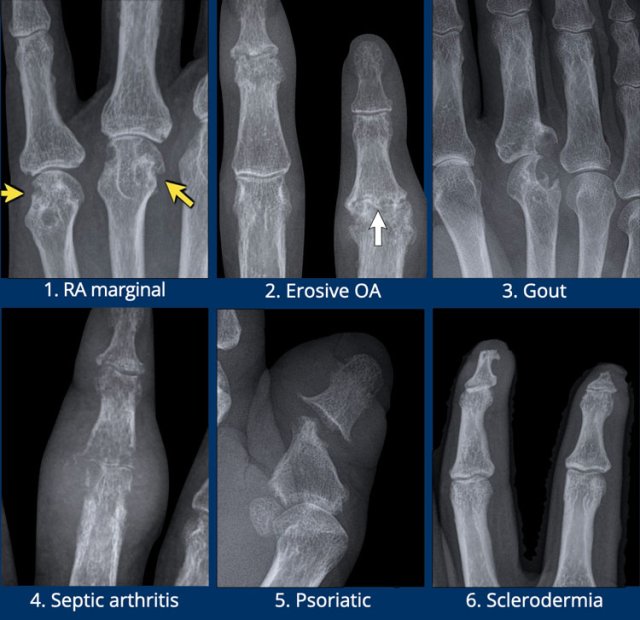

Typical examples of specific erosion patterns

1. Rheumatoid arthritis.

Typical marginal erosions in MCP-joints.

2. Erosive osteoarthritis.

Subchondral erosions in DIP- and PIP-joints. The concurrent formation of osteophytes results in a gull-wing deformity.

3. Gout.

Eccentric erosion with an overhanging edge. The sclerotic margin in this case indicates chronic and indolent disease.

4. Infection.

Destructive changes with cartilage loss and erosions.

5. Psoriatic arthritis.

Bony erosions narrowed the end of the proximal phalange as a “pencil”, which rests in the “cup” formed by the expanded base of the distal phalanx as a result of bony proliferations.

6. Scleroderma.

And other multisystem disorders can produce erosions at the distal tufts, this is called acro-osteolysis.